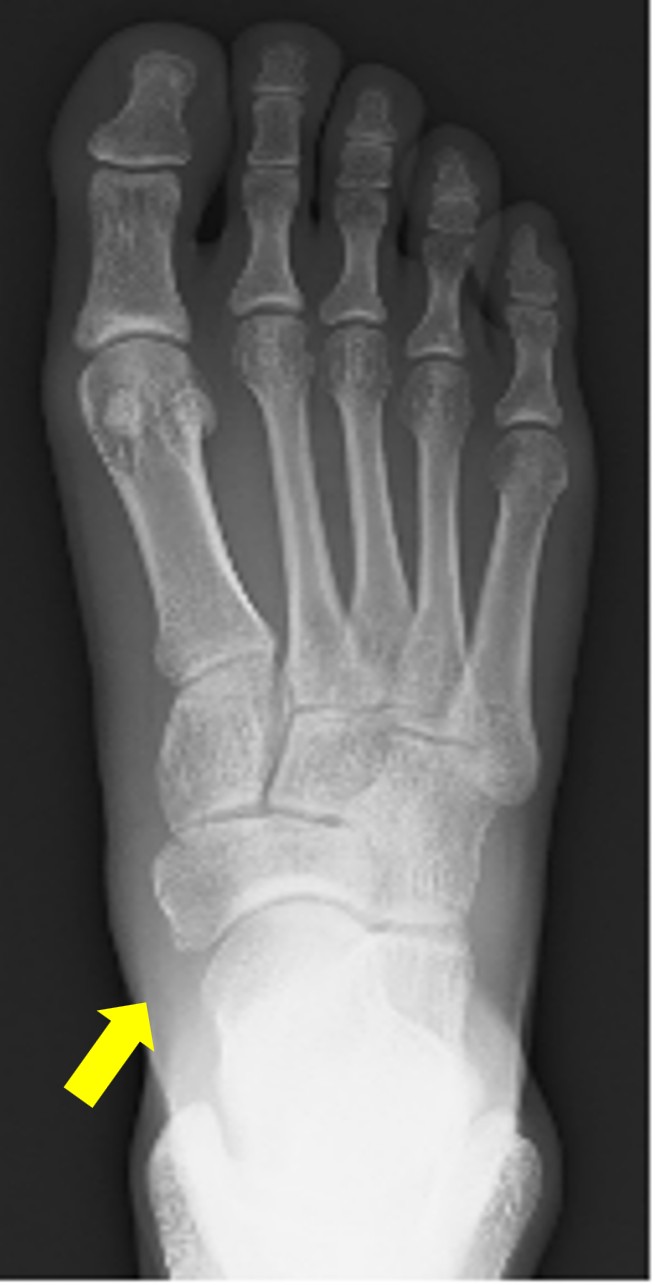

有痛性外脛骨

術後レントゲン写真(外脛骨がなくなっている)